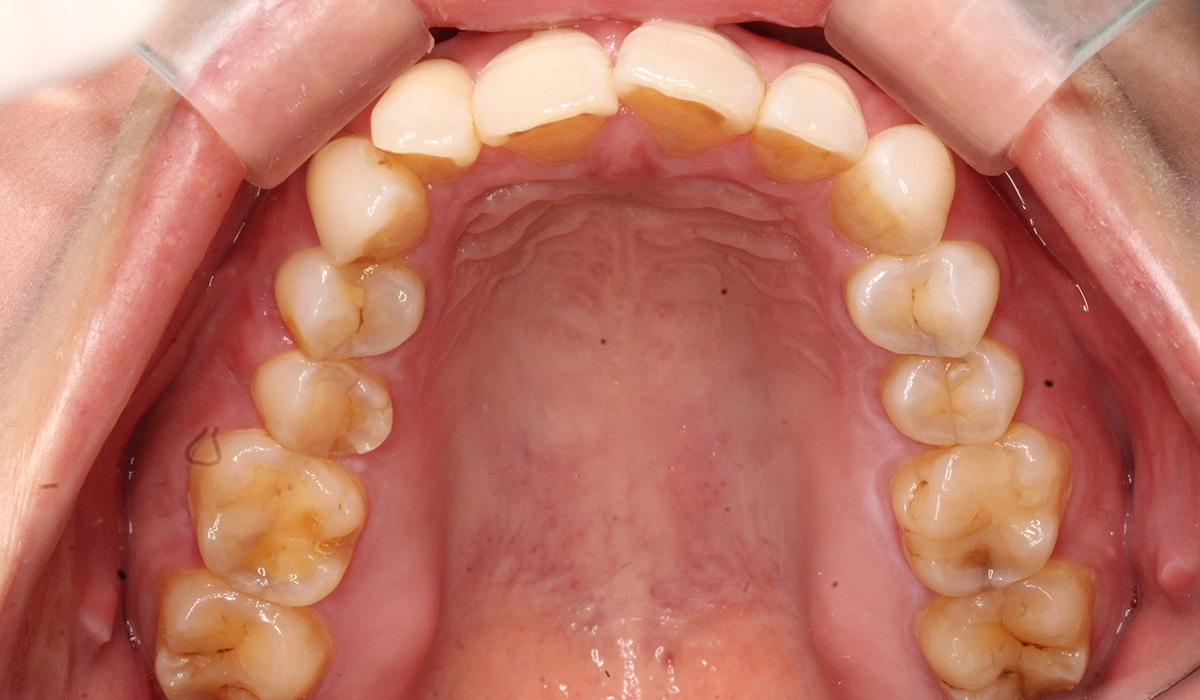

術前:上顎